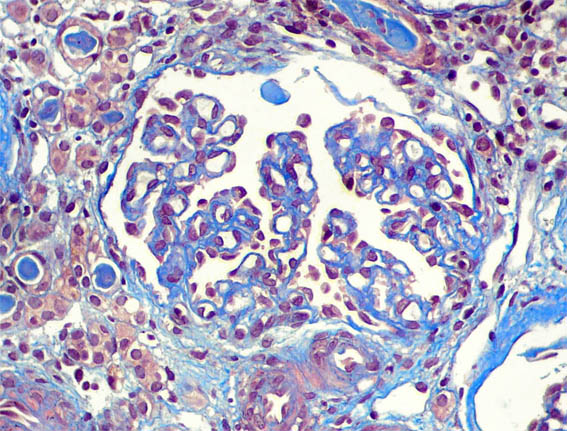

Figura 3.

Tricrómico de Masson, X200.